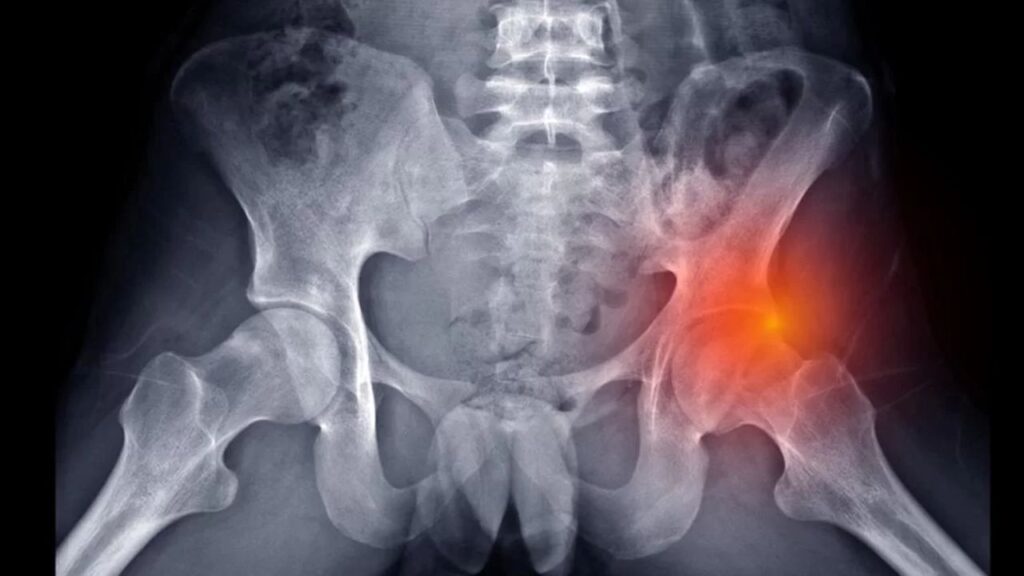

Exames e avaliação ortopédica A avaliação começa com testes físicos específicos de impacto, realizados pelo especialista no consultório para reproduzir o desconforto. Como as radiografias simples não mostram o labrum, a ressonância magnética (preferencialmente a artrorressonância em casos específicos) é o exame padrão-ouro. Ela permite visualizar a localização exata da ruptura, a presença de cistos associados e o estado da cartilagem adjacente, essencial para o planejamento terapêutico.